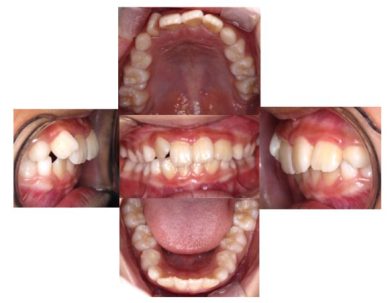

治療開始から10か月→

この男の子は10か月間でここまで改善しました。まだまだ、改善途中ですがお子さんの成長を利用すると短期間で改善が期待できます。この子が10か月間やってきたことは?

- 起きているときに1時間マイオブレイスをお口にいれる(テレビを見ながら)、寝るとき入れる。

- 1日5分間動画を見ながら口周りの悪い癖を取るトレーニングをすることだけです。

それによって顎の骨の成長方向と成長量を改善できた結果、歯並びもここまで改善しました。